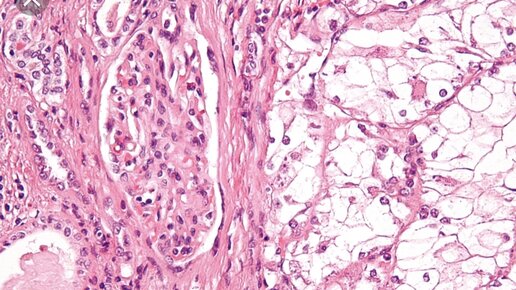

Базальноклеточный рак (базалиома) – это поверхностная медленно растущая папула или узелок, возникающий из определенных клеток эпидермиса. Базальноклеточные карциномы возникают из кератиноцитов вблизи базального слоя, которые можно называть базалоидными кератиноцитами. Течение индолентное, может рецидивировать, но редко метастазирует. Локальный рост может сопровождаться выраженной деструкцией. Диагноз ставится на основании данных биопсии. Лечение зависит от характеристик опухоли и может проводиться...